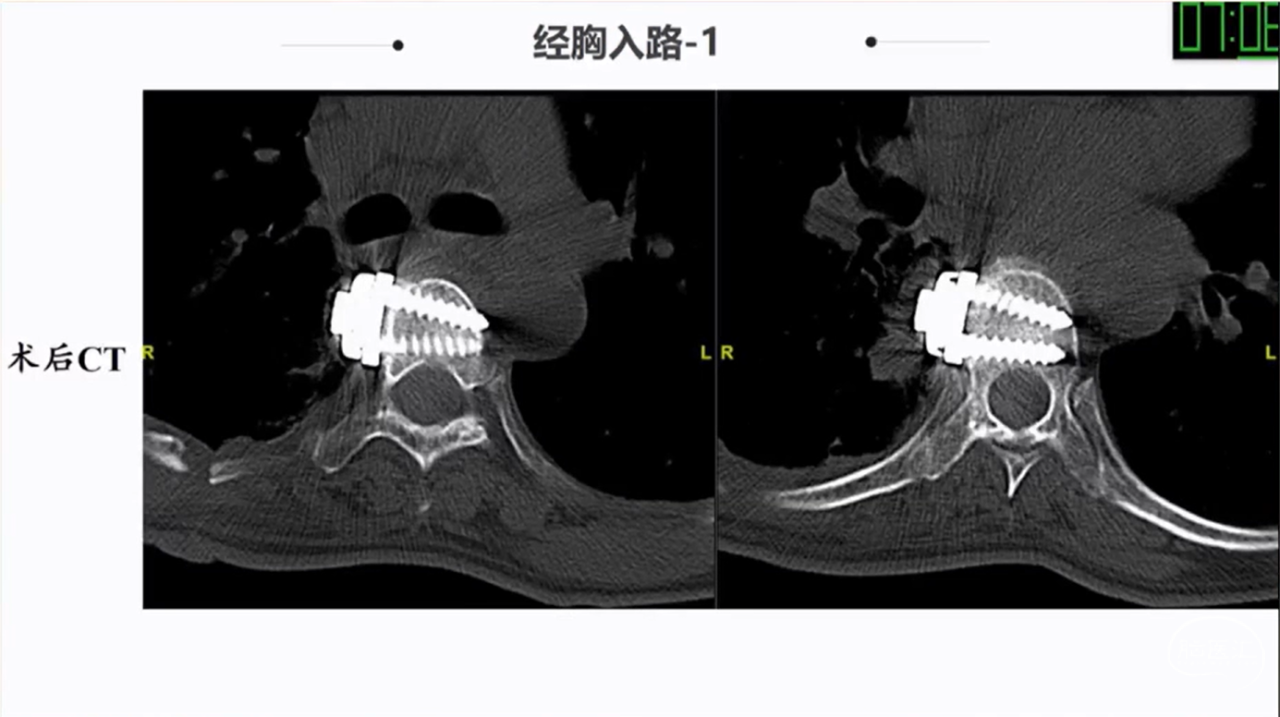

椎旁肿瘤种类多样,手术切除是主要的治疗方法;血供一般,病灶内切除减容,为肿瘤的全部切除提供有利条件;Witlse入路治疗椎旁巨大肿瘤优势明显;椎体破坏、血管侵犯、胸膜下的病例尽量选用经胸入路或者联合入路。

· 椎体破坏、血管侵犯、胸膜下的病例尽量选用经胸入路或者联合入路